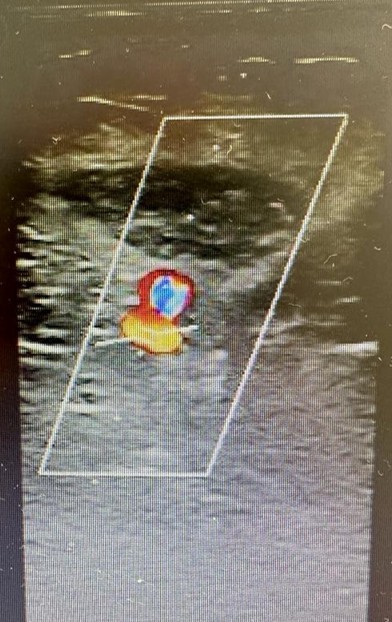

A las cuarenta y ocho horas del postoperatorio el paciente consultó por un cuadro de inflamación infrapatelar de la pierna izquierda. Ante la sospecha de una trombosis venosa profunda, se lo derivó de forma urgente a la guardia, donde se le realizó un ecodoppler venoso. El estudio descartó un proceso flebotrombótico, pero evidenció un hematoma que contenía signos compatibles con un pseudoaneurisma dentro del hematoma (Figs. 1 y 2). Frente a este hallazgo, se decidió realizar de manera urgente una angiografía del miembro inferior izquierdo, la cual confirmó la presencia de un pseudoaneurisma en una rama de pequeño calibre de la arteria poplítea, secundario a laceración traumática de dicho vaso (Fig. 3). En el estudio hemodinámico no se evidenció extravasación de contraste a nivel del pseudoaneurisma, motivo por el cual el equipo de hemodinamia lo consideró indemne.

Figura 2. Ecodoppler, en la parte inferior se observa la curva de flujo en vaivén, en el cuello del pseudoaneurisma. Lo marcado en rojo es el punto donde se detecta el flujo

Figura 3. Arteriografía desde arteria poplítea derecha que confirma pseudoaneurisma de 13 mm de diámetro, del ramo genicular